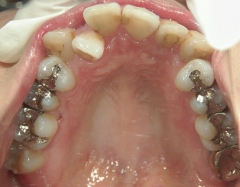

矯正歯科 治療後矯正歯科 全顎ワイヤー矯正 治療後矯正歯科(全顎ワイヤー矯正)治療後

28歳女性 浜松市中区在住

治療期間2年6ヶ月

矯正歯科 治療前 外科手術併用(コルチコトミー)、非抜歯